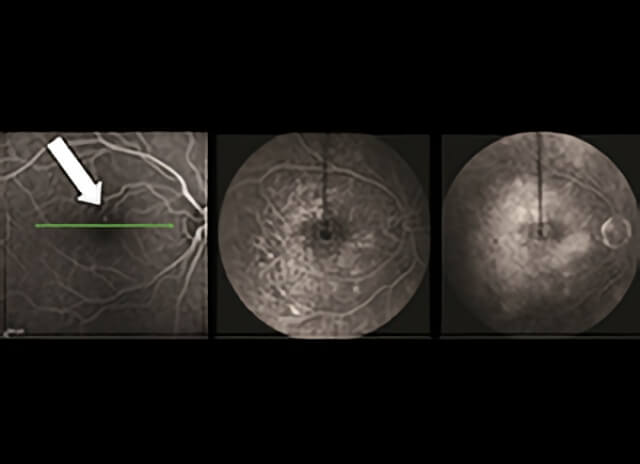

Fluorescein angiography: Macular edema may be seen as a pinpoint leak (left, large arrow) in mild cases. In serious cases, macular edema may diffusely involve the macula. Note how the image becomes brighter and more diffuse as more dye leaks from damaged macular capillaries (center and right). (Images courtesy of the ASRS Retina Image Bank, contributed by Dr. Suber Huang)

Fluorescein angiography and optical coherence tomography are 2 common tests to evaluate macular edema. Based on the appearance of fluid on these tests, macular edema may be widespread, localized, or be made up of many small blisters surrounding the center of the macula—a common form called cystoid macular edema.